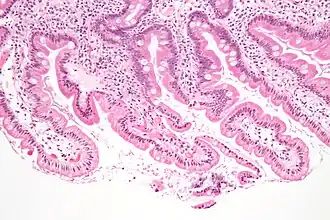

Sección de duodeno de gato -

Anatohistológicamente el duodeno cuenta con 5 capas:

- Túnica serosa o peritoneal

- Tela subserosa

- Túnica muscular

- Tela submucosa

- Túnica mucosa